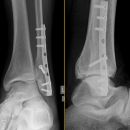

Osteosynthesis

Sprunggelenk